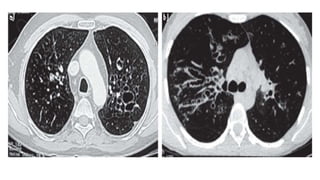

categorized as Cylindrical or Tubular (the

most common form), Varicose & Cystic.

Cylindrical or Tubular

Varicose

Cystic